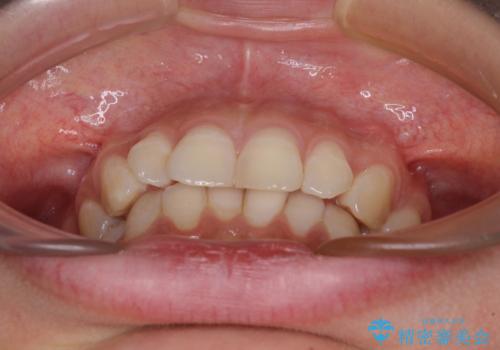

- 下顎の前歯が隠れていることと、デコボコを気にして来院された患者様です。

咬み合わせと目立っていた銀歯が改善され、患者様には大変満足していただきました。